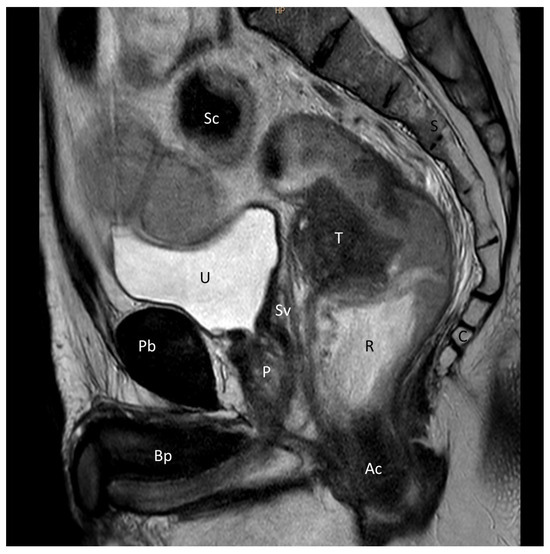

2.2. Anatomical Critical Point Description

- The shortest distance between the anterior surface of the rectum and the membranous urethra (R-Mu distance);

- The distance between the point on the anterior wall of the rectum closest to the membranous urethra and the anal margin (R-Am distance);

- The angle formed by the intersection of the axis of the anal canal and the axis of the rectum (anorectal angle).